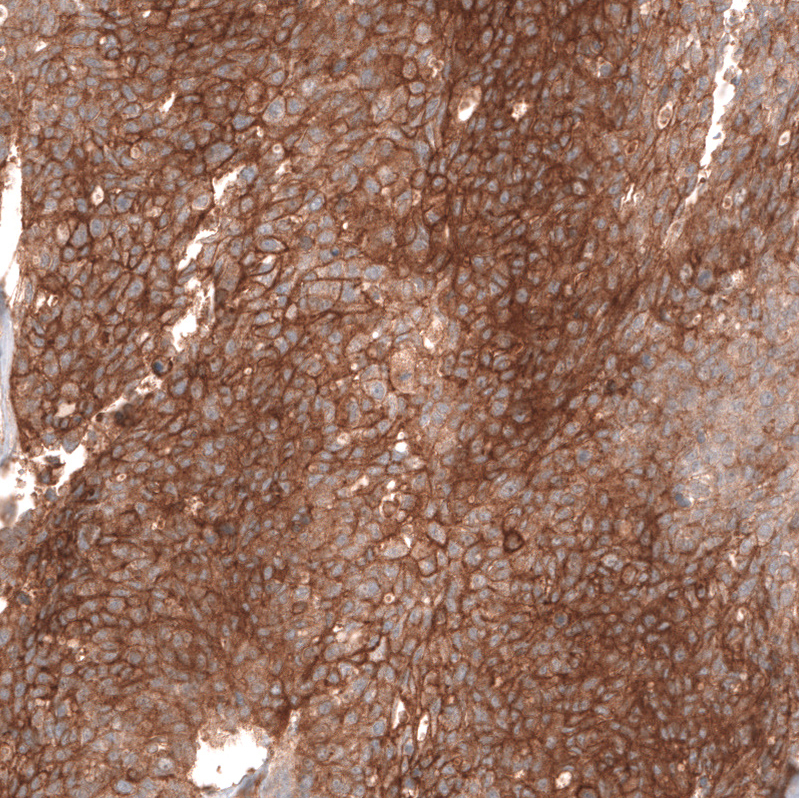

Immunohistochemical staining of human ovarian cancer (high grade serous carcinoma) shows strong membranous positivity in tumor cells.